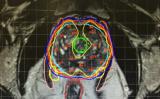

合肥离子医学中心项目正式交付 打造世界先进、国内一流的质子治疗机构

质子治疗项目方面,合肥离子医学中心工程建设项目正式交付,预计2020年下半年进入临床试验阶段,项目建成后每年可治疗约2000例患者。国产化系统研发方面,目前已进入设备集成总装和工程调试阶段。 2020-04-10 产业应用

未来在免疫PET显像领域可能会获得突破性的进展

近日,上海交通大学医学院附属仁济医院核医学团队、美国威斯康星大学麦迪逊分校(UW-Madison)团队受邀在国际顶级化学学术期刊《Chemical Reviews》 《化学综述》(IF=54 301)撰写了论文,详细阐述了免疫PET显像探针的设计构建流程。 2020-04-04 产业应用